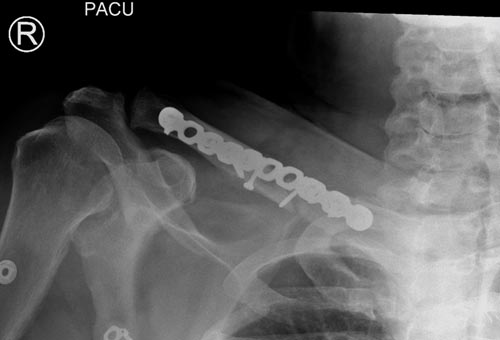

Уважаемые коллеги. Обратился пациент 29лет, оперирован в 2007 г. в Республиканском центре по поводу перелома ключицы и/м спицей, после несращения повторно оперирован в 2008 году, со слов больного освежение и повторно фиксация спицами, и обратился только через 6 лет, активные и пассивные движения в правом плечевом суставе в полном объеме, беспокоит только слабость при поднятии тяжести и подвижность в с/з ключицы. Р-снимок прилагается.Честно признаться, пока не знаю, что делать, имеются обычные пластины из ЦИТО, спицы, может, краевая резекция до появления «росы» дефект заполнить спонгиозной костью, фиксация и/м двумя спицами, загнуть оба конца спицы с компрессей, или пластина…или вообще не трогать. Прощу не критиковать, имеем то, что имеем, пациент в НИИТО не может ехать из-за финансов. С уважением Абдурашид.

Освобожден средний фрагмент и боковая компрессия лагированием, фиксация пластиной..